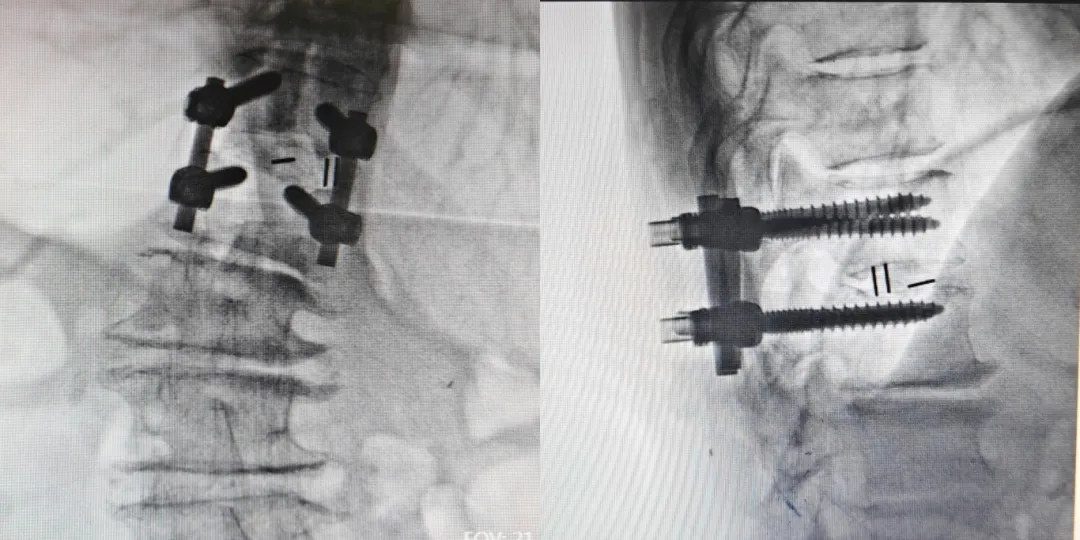

在急诊科、影像科、手术麻醉科、介入科、心血管内科等多科室的紧密协作下,术前评估迅速完成。当晚,在主任惠华的指导下,手术团队为袁奶奶施行了胸腰椎后路减压间盘切除植骨融合内固定术(T12/L1)。手术室内,无影灯下,医生们屏息凝神,像在刀尖上起舞,精准地去除了压迫脊髓的“罪魁祸首”。

术中团队倾力合作和精细操作

术后压迫彻底解除,融合内固定位置满意